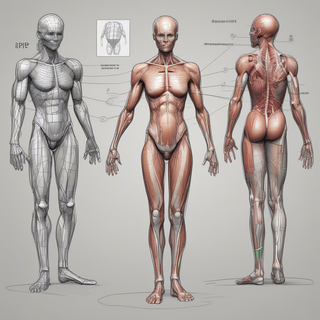

Generate ultra-realistic microscopic imagery for medical research.Open

Generate ultra-realistic microscopic imagery for medical research.Open